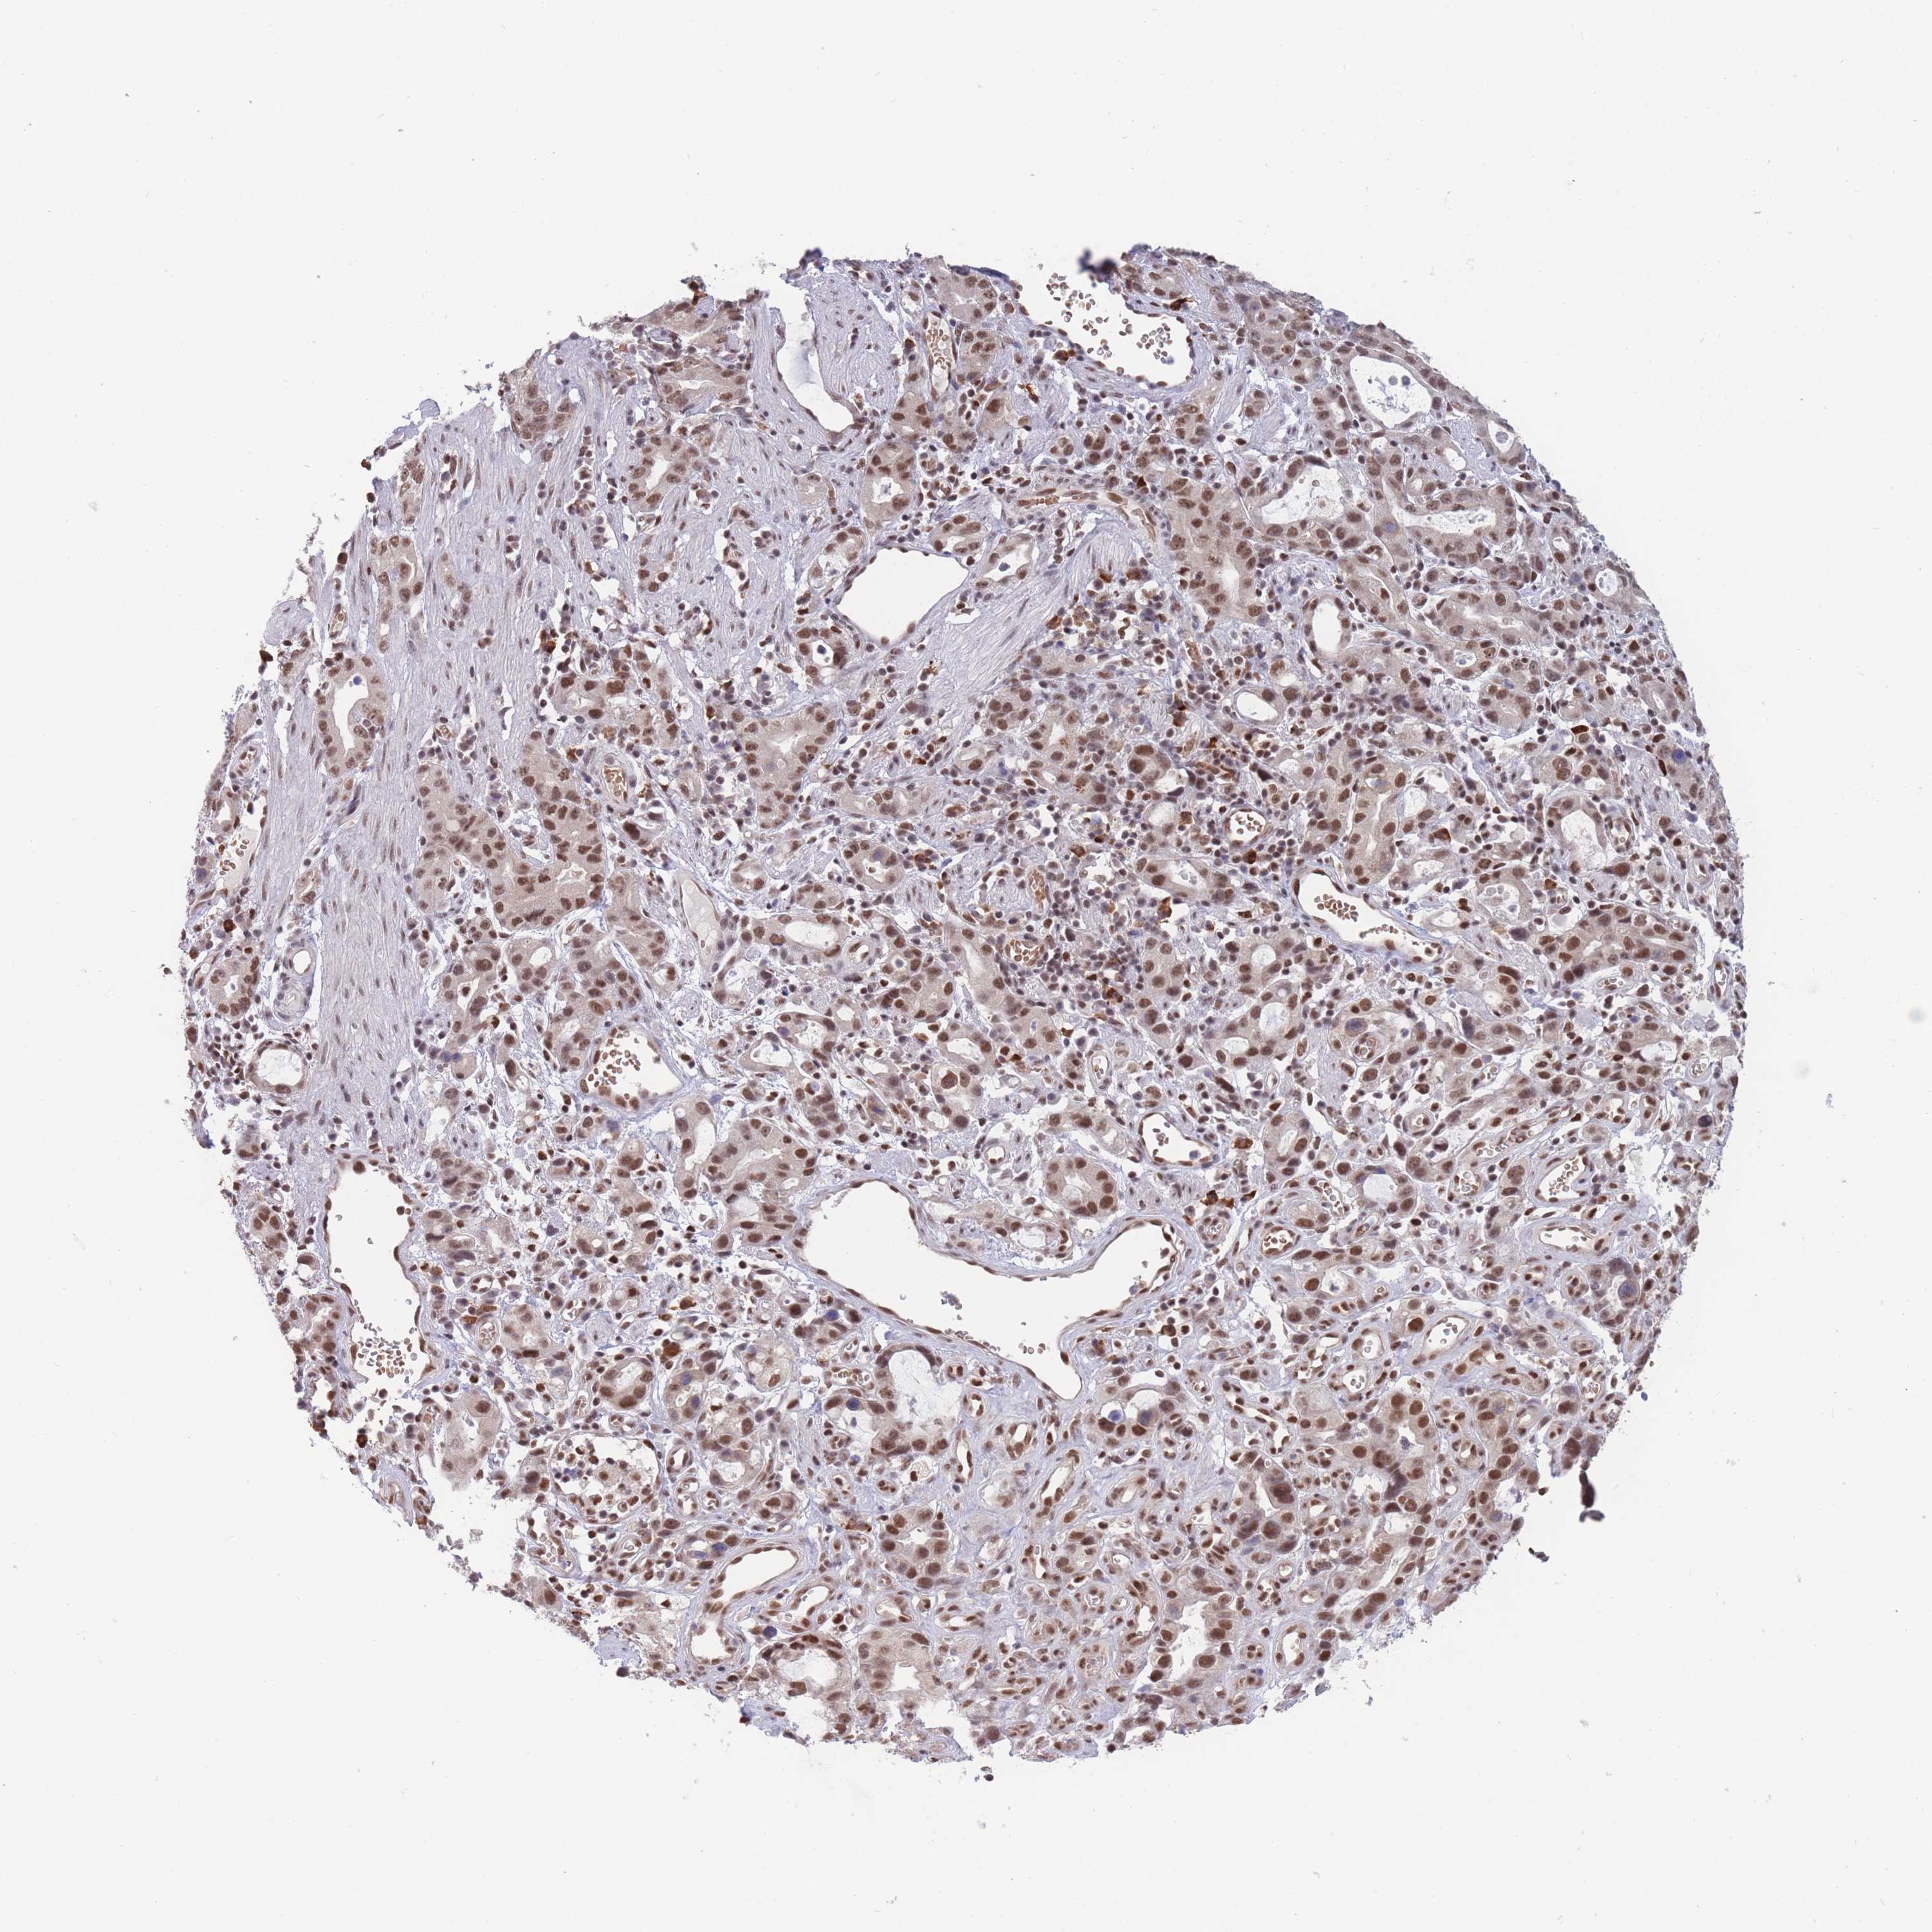

STOMACH CANCER - Protein expressioni

A mouse-over function shows sample information and annotation data. Click on an image to view it in a full screen mode. Samples can be filtered based on level of antibody staining by selecting one or several of the following categories: high, medium, low and not detected. The assay and annotation is described here.

Note that samples used for immunohistochemistry by the Human Protein Atlas do not correspond to samples in the TCGA dataset.

Antibody stainingi

Antibody staining in the annotated cell types in the current human tissue is reported as not detected, low, medium, or high, based on conventional immunohistochemistry profiling in selected tissues. This score is based on the combination of the staining intensity and fraction of stained cells.

Each image is clickable and will lead to virtual microscopy that enables deeper exploration of all samples and also displays staining intensity scores, fraction scores and subcellular localization as well as patient and tissue information for each sample.

Antibody HPA031162

Antibody CAB009119

Staining

High

Medium

Low

Not detected

Intensity

Strong

Moderate

Weak

Negative

Quantity

>75%

75%-25%

<25%

None

Location

Nuclear

Cytoplasmic/membranous

Cytoplasmic/membranous,nuclear

Adenocarcinoma, NOS

Adenocarcinoma, High grade